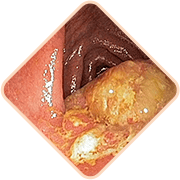

Las hemorroides pueden estar relacionadas

con otras condiciones del área rectal que

requieren atención médica para un

diagnóstico adecuado y tratamiento

oportuno.

Los vasos sanguíneos en las hemorroides pueden ser más sensibles y en algunos casos presentar sangrado. La intensidad puede variar y es importante buscar orientación profesional cuando sea necesario.

En algunos casos, las hemorroides persistentes pueden requerir atención para prevenir complicaciones. La consulta con un profesional de la salud puede ayudar a determinar el abordaje más adecuado para cada situación individual.